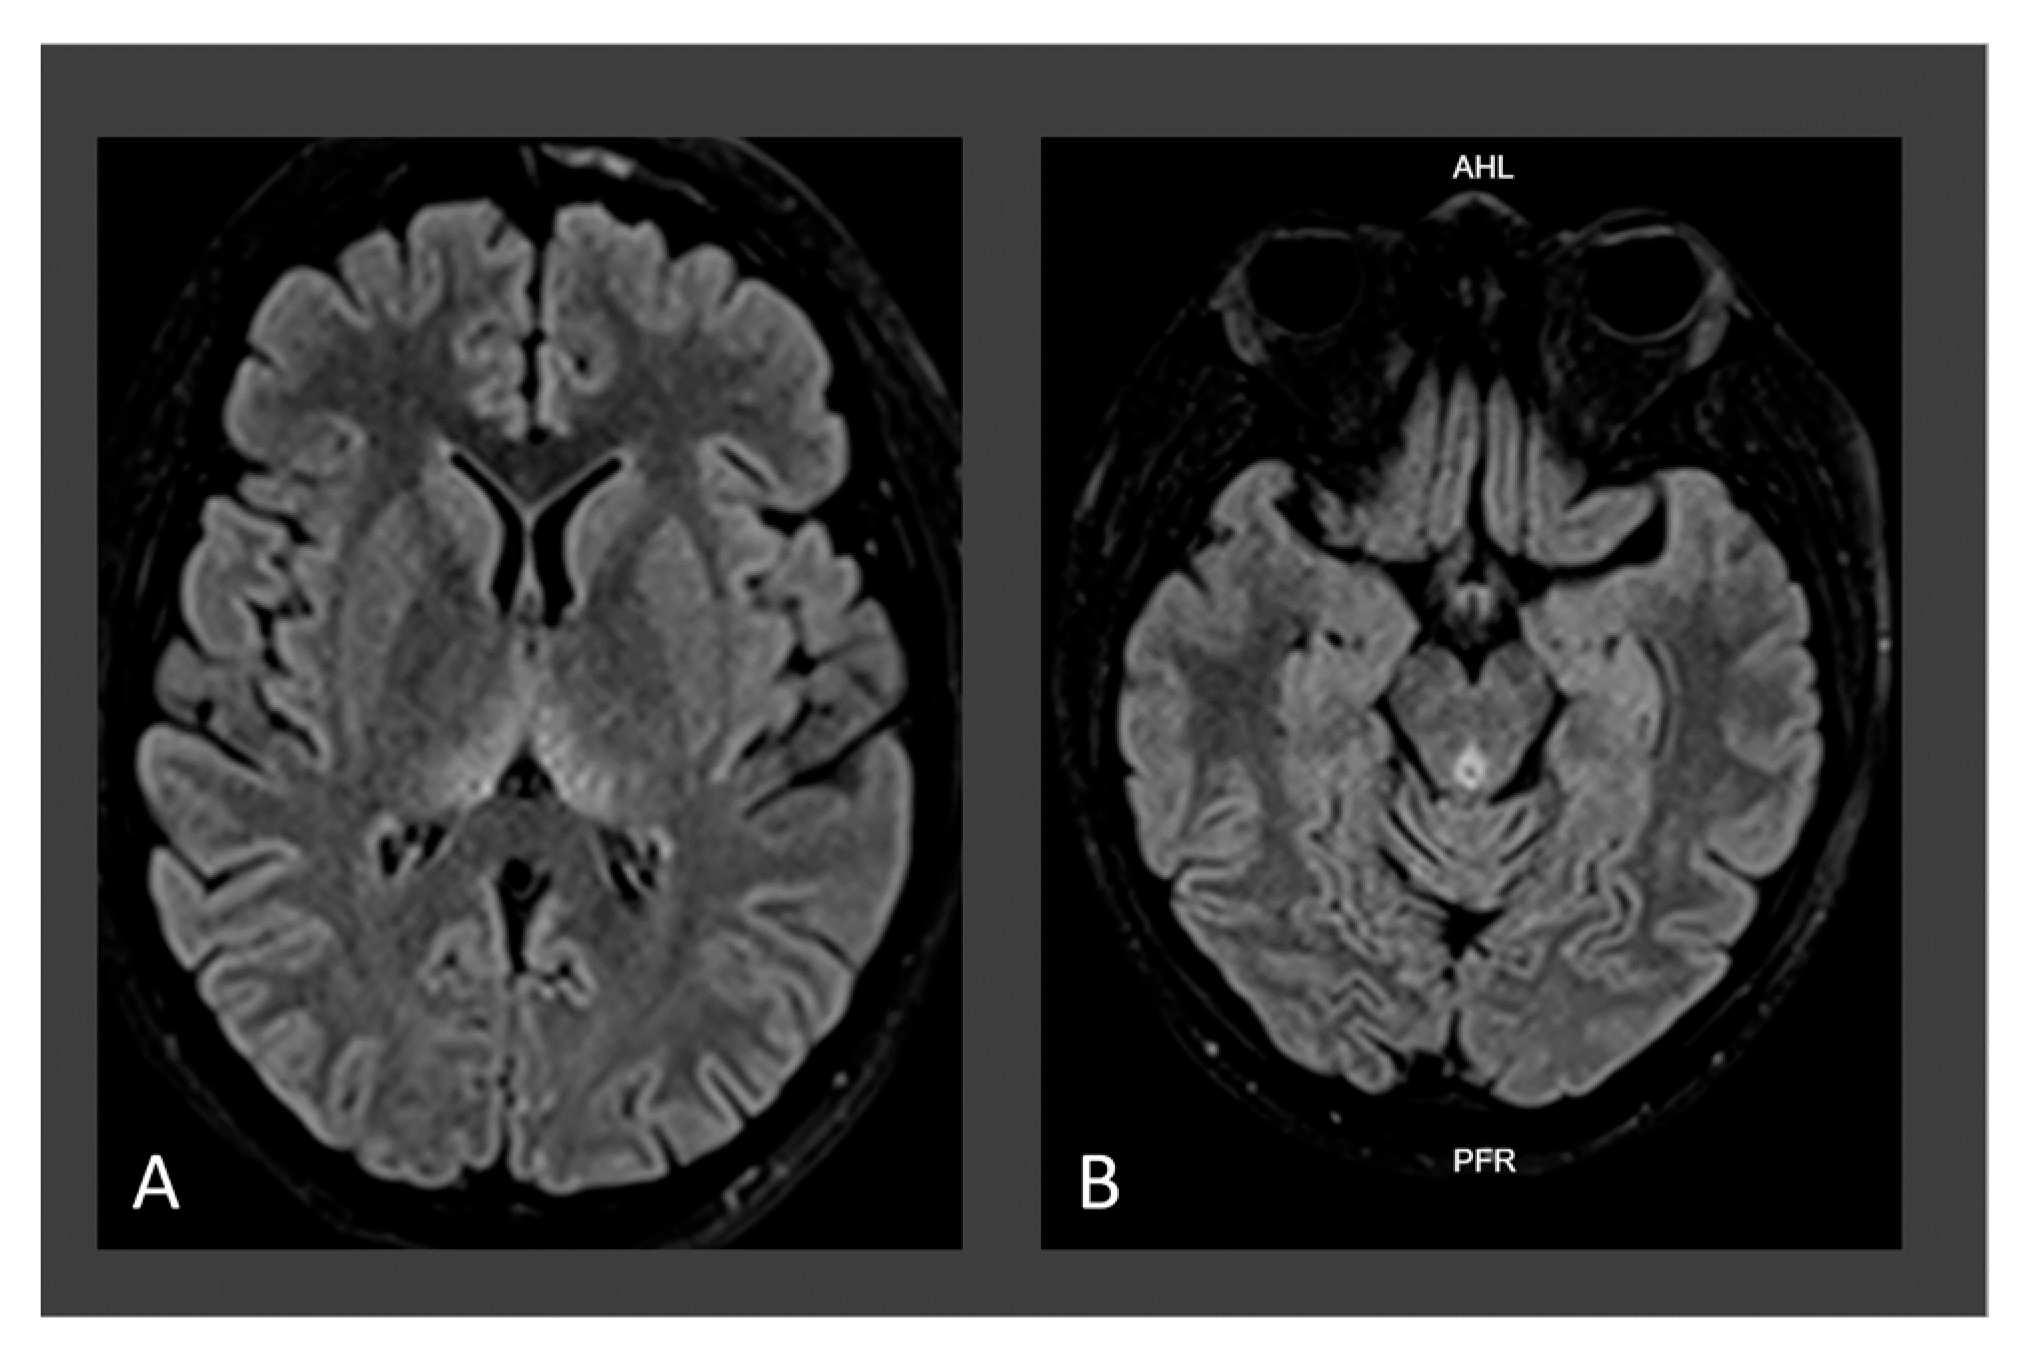

| Neuroimaging for W.D. | Typical | Typical | Typical |